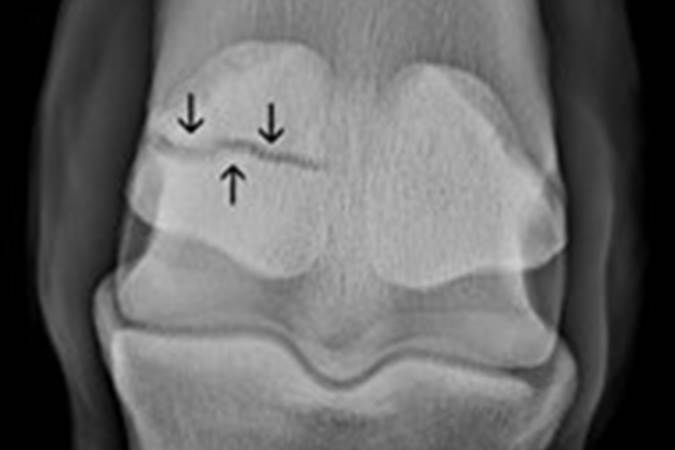

Focus on Fractures

This month’s fracture is a 4 year old gelding in jump race training which sustained a mid-body fracture on its left hind medial proximal sesamoid bone.